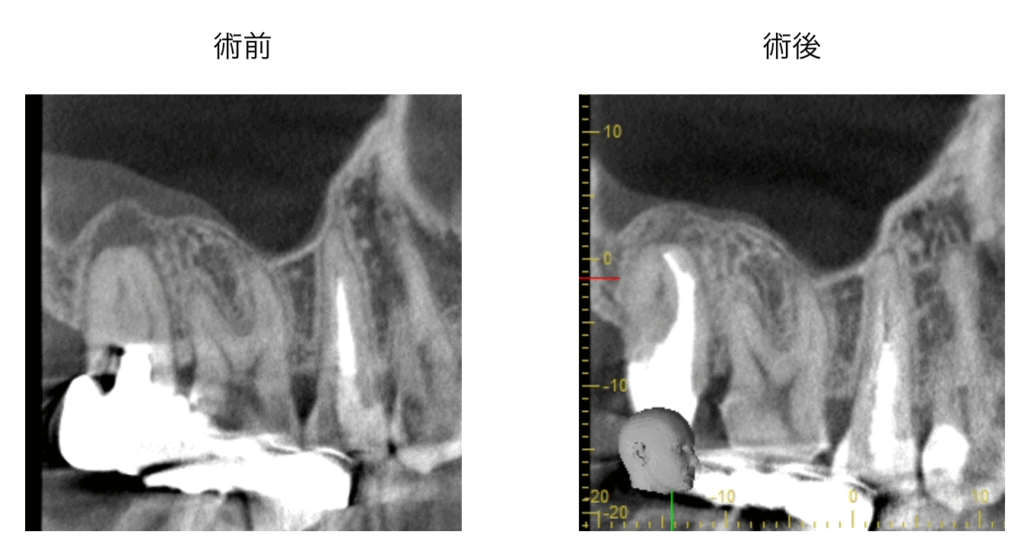

MTAセメントとは?|生体にやさしく神経を守る歯科材料

MTA(Mineral Trioxide Aggregate)セメントは、歯科医療で使用される生体親和性の高い薬剤です。

● MTAの主な特徴

細菌…